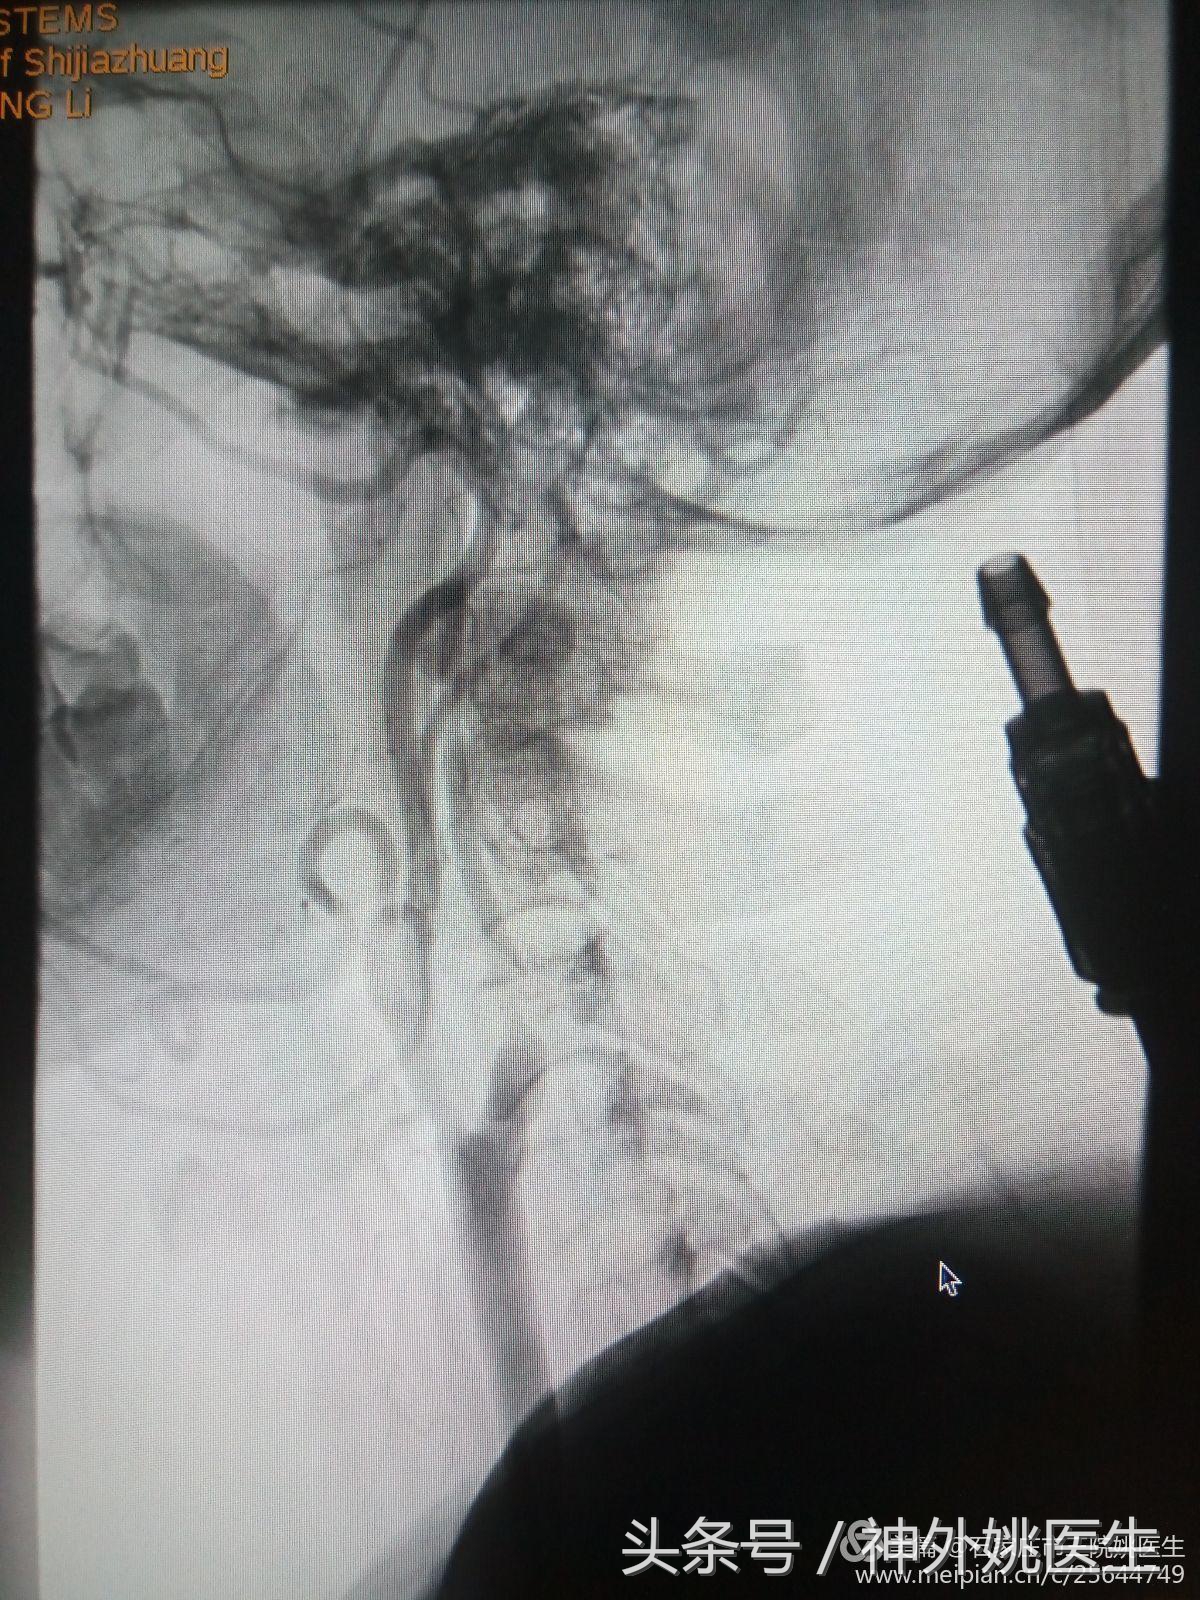

术前评估(DSA):

1.右颈动脉造影示:右颈内动脉狭窄部位位于球部以远,狭窄远端管腔明显变细(图6、图7)。狭窄段远端平下颌角及C2/3椎间盘水平(图8)。提示位置较高,操作难度较大。缝合时需精细操作,避免管径丢失,术后管腔狭窄。

(图8)